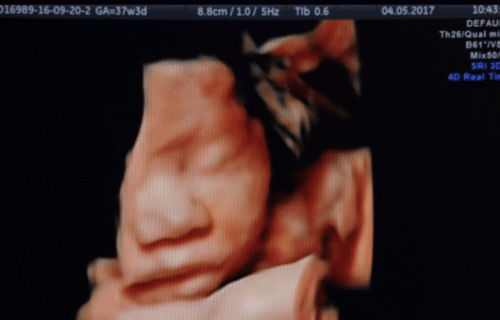

바이오 IVF alone can’t save us from a looming fertility crisis 저출산율 문제 해결, 체외 수정만이 답이 아니다 전 세계적으로 심각한 문제가 되고 있는 저출산율을 높이는 데 체외 수정 같은 불임 치료 기술보다 가족 친화적 정책과 성평등이 더 효과적일지 모른다.